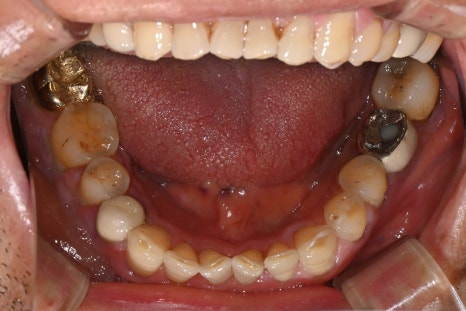

The image on the left is a panoramic X-ray taken at the initial visit, and the image on the right is an intraoral photo of the patient.

The lower right molar (#47) showed significant bone loss around the gum on the X-ray, and the tooth was very loose, so we were planning #47 extraction and implant treatment along with full gum treatment.

However, during scaling, there was more bleeding than expected and hemostasis was not going well,

so we provided only simple treatment and the patient went home for the time being.

The next day, after deciding on treatment, we performed extraction of the lower right molar (#47), and severe bleeding occurred again during the procedure.

Based on the judgment that "this is not just simple inflammation,"

we immediately collected some gingival tissue and performed a biopsy and blood test together.

As a result, the findings suggested suspected leukemia rather than simple inflammation.